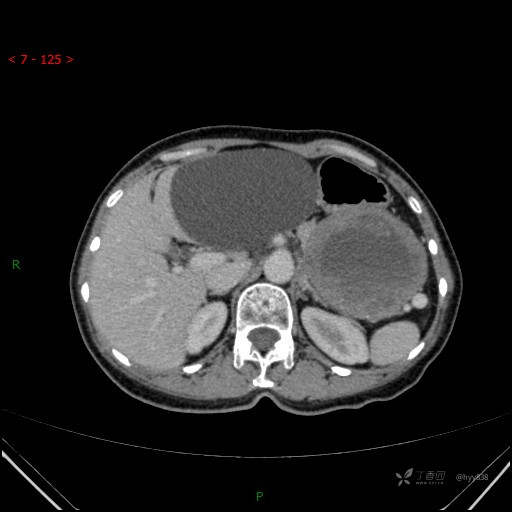

增强动脉期